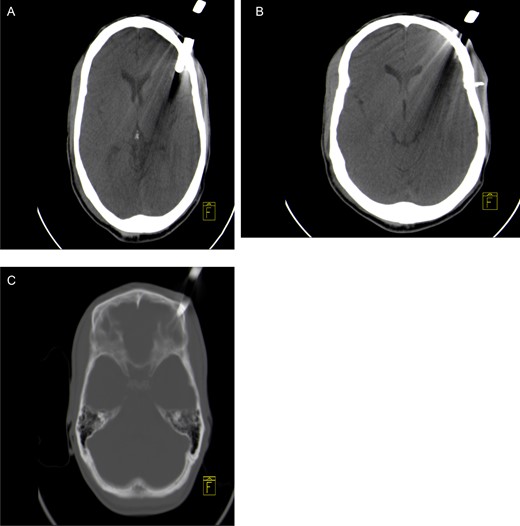

A 30-year–old male patient was stabbed in the head with a garden fork following a dispute with a neighbour. He was initially assessed at his local hospital, which referred him to our neurosurgery unit for further management. On arrival, he was haemodynamically stable and was noted to have a retained garden fork in the left frontal area. His Glasgow Coma Scale (GCS) was 14/15, with no associated neurological deficits. He was noted to have left peri-orbital swelling, but vision was intact. There was no active bleeding from the wound and no other associated injuries. He was intoxicated at the time of examination and had a generalized tonic–clonic seizure in the emergency department, which was aborted. He was loaded with phenytoin and put on maintenance therapy. A computerized tomographic (CT) scan of the brain showed a retained garden fork in the frontal area (Fig. 1). The garden fork prong had penetrated the left frontal cortex; however, it caused a lot of artefact making visualization of parenchymal tissue damage difficult to appreciate (Fig. 2). Tetanus toxoid was administered and he was taken to the operating theatre for removal of the garden fork under general anaesthesia. At induction, intravenous first-generation cephalosporin and metronidazole were administered for prophylaxis.

Axial non-contrast CT brain scan showing a garden fork prong in the left frontal parenchyma with associated artefact (A) and loose bone fragment in left frontal soft tissue (B). Axial CT bone window showing left frontal bone fracture caused by the fork (C).